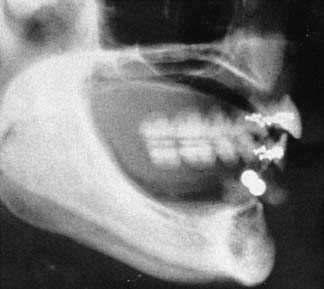

Radiographic evaluation is also necessary. The best initial film is the panoramic view. However, there can be variations in magnification (5% to 35%); a small radiopaque reference object should therefore be placed near the proposed implant placement site during the exposure (Fig. 13-5). Measurement of this image on the actual radiograph enables the practitioner to correct for any magnification error (Fig. 13-6). A ball bearing placed in wax on a denture baseplate or in polyvinyl siloxane impression putty works well. Some new panoramic radiography machines have standardized enlargement ratios, which makes correction markers less necessary.

Fig. 13-6 A panoramic radiograph exposed with the ball bearings positioned intraorally with a wax or resin baseplate.